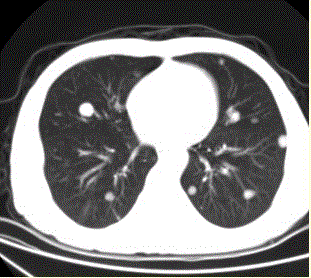

问题 患者男,45岁,因肝硬化、肝癌行肝移植术后6个月,咳嗽2周,来院复查。CR及CT影像如下图。 该疾病的转移途径可以为

选项 A.经肺动脉 B.经肺动脉至淋巴管而后到肺外围 C.经纵隔淋巴结逆流到肺门淋巴结,再经肺内淋巴管到肺外周 D.经胸膜腔 E.经气道 F.经支气管动脉

答案 ACDE